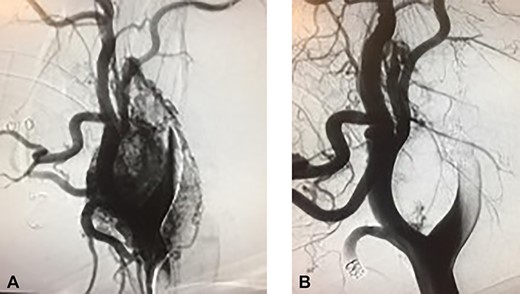

Incision was made from the angle of the mandible towards the chin and subplatysmal flaps were created. The common carotid artery was dissected to obtain proximal control. Distal control was obtained by exposing the internal carotid artery and the ECA cephalad to the tumor (Fig. 3). The tumor was adherent to the posterior wall of the carotid bifurcation, requiring en-bloc resection (Fig. 4) with reconstruction using a common carotid to internal carotid bypass performed with a 6-mm polytetrafluoroethylene (PTFE) interposition graft (Fig. 5). The hypoglossal, vagus and glossopharyngeal nerves were identified, meticulously dissected and preserved. The patient recovered well, had hoarseness of the voice, which resolved after few months with no intervention. The tumor pathology revealed an extra-adrenal paraganglioma positive for chromogranin, synaptophysin and S-100.

(A) Tumor at the bifurcation. Transected common carotid artery. (B) CBTs. (C) Internal carotid artery.